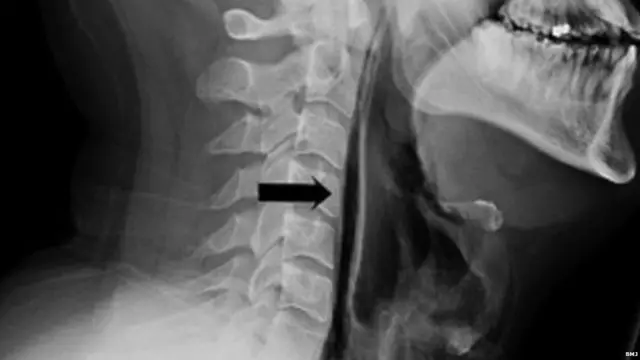

ઇમેજ સ્રોત, BMJ

એક્સ-રેમાં જાણવા મળ્યું કે છીંક રોકવાના કારણે દબાણ પડતાં શ્વાસનળીની કોશિકાઓ ફાટી ગઈ છે.